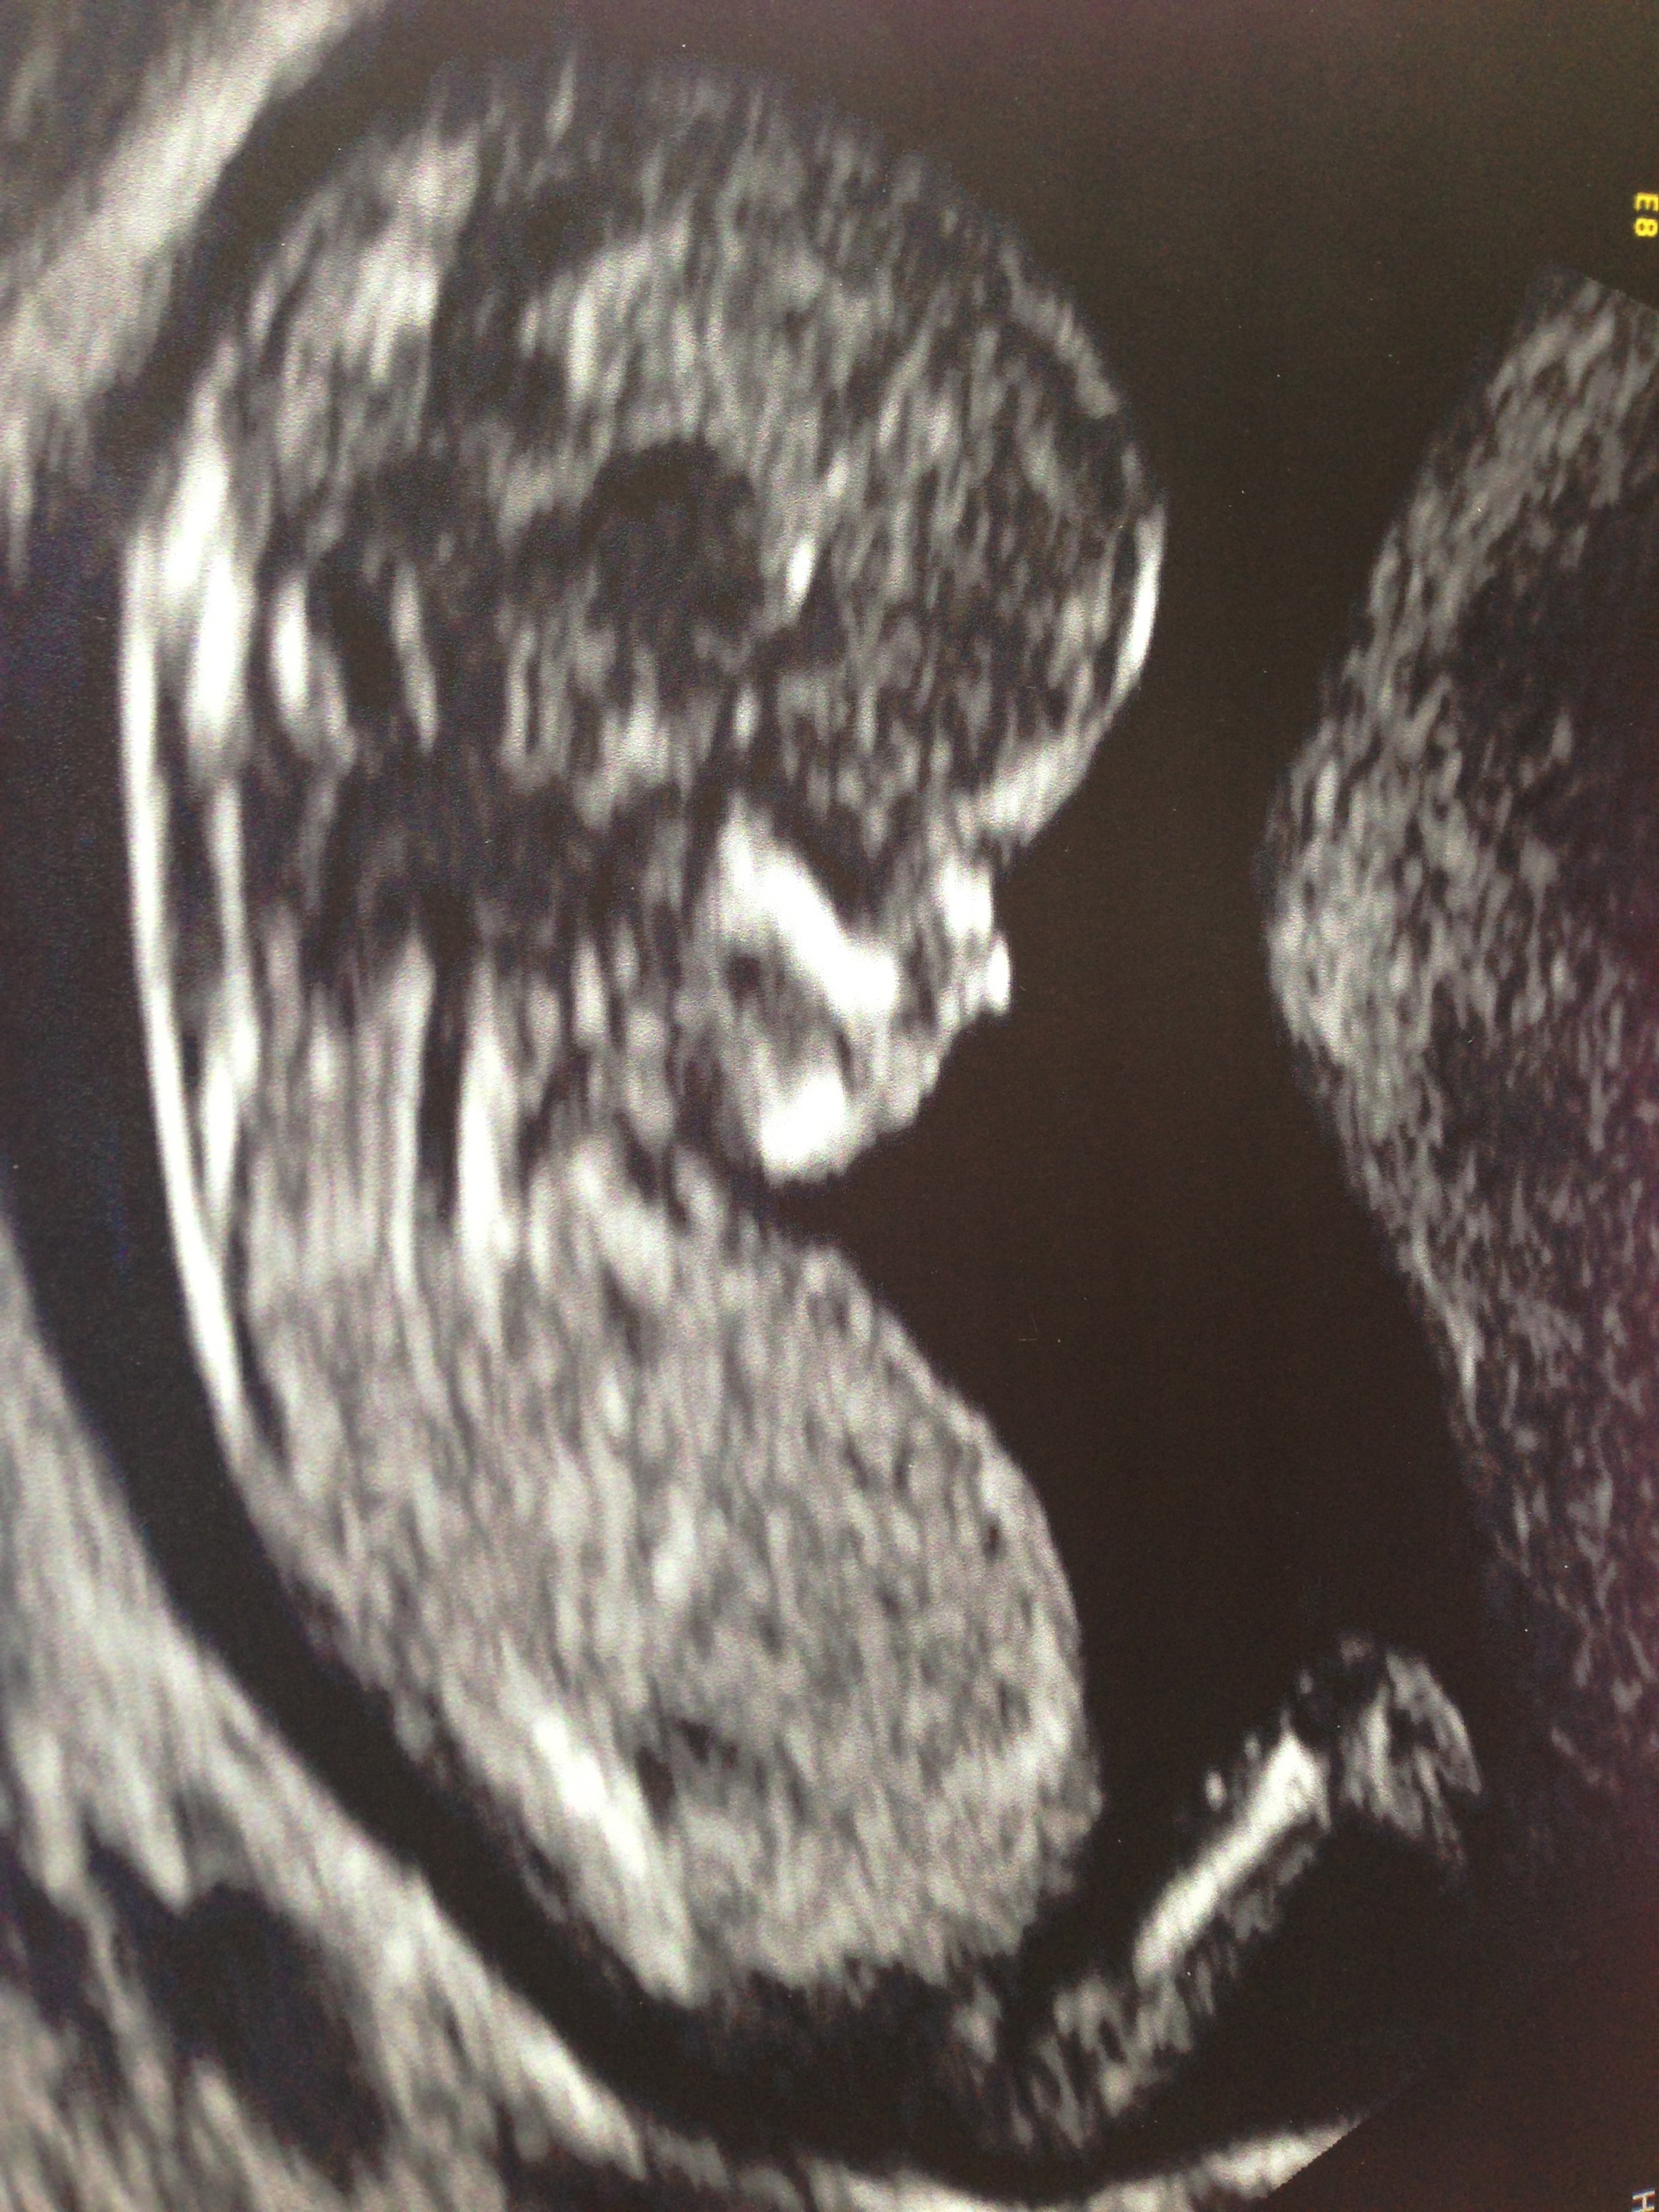

Girl or Boy nub! Please guess!

These ultrasound pictures were taken when baby was 12weeks and 5days. Guesses would be greatly appreciated, thank you. Name:  IMG_3074.jpg

I think girl xx

I think girl on second pic (lower upload).

If that is the nub (on the newer pic), I think girl since it is long and pointed downwards.

Girl guess from me!